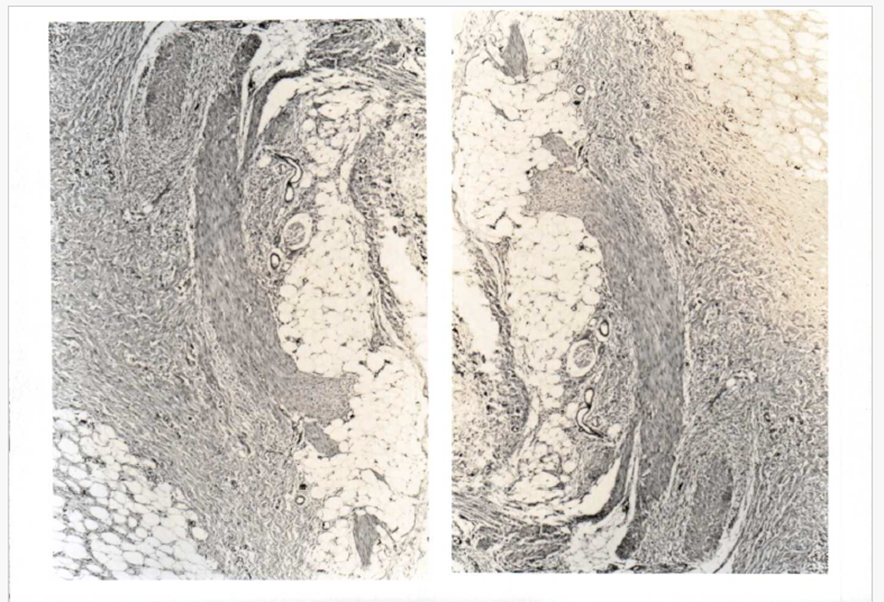

A biopsy was performed (Figure 1). Microscopy revealed a tumour composed of bundles of dense interlacing fibrous tissue containing fat and islands of loose, whorled, mesenchymal-like cells in a mucoid-appearing matrix. The fibrous component was characterized by a rippled, swirling pattern without evidence of mitosis. Fatty elements resembled mature adipose tissue. Islands of loose mesenchymal-like cells stood out as translucent bluish foci contrasted to the dense eosin-staining fibro collagenous stroma. Masson's trichrome Mucicarmine staining induced a pale stain yielded a rich green fibrous stroma. Pink colour in the matrix of the mesenchymal component. Reticulum stains demonstrated fine wavy fibrils in these foci. A diagnosis of fibrous hamartoma of infancy was established, and the entire tumour was therefore resected. The surgical specimen measured 7 x 2 x 1 can and was lipomatous- appearing with fibrous areas, and partially encapsulated. (Figure 2) A pedicle of tumour was found to extend between the plantar fascia and the inferior surface of the os calcis to reach the lateral border of the foot. The dissection was performed en toto. Neurovascular structures could not be identified. Measurement, including the pedicle, was 7 x 2 x 1 cm. The surface was gray, firm, and glistening.

Figure 1. Microscopic picture characterized by bundles of interlacing fibrous tissue containing fat and islands of mesenchymal-like cells. (430x)